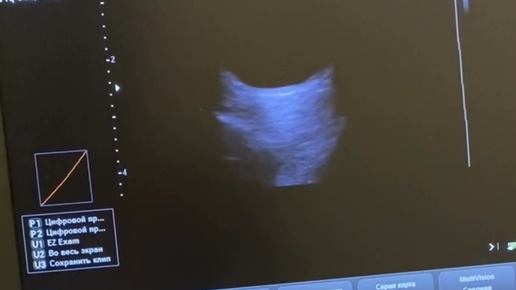

транспарпебральное узи глазного яблока

Врач - офтальмолог первой кв категории